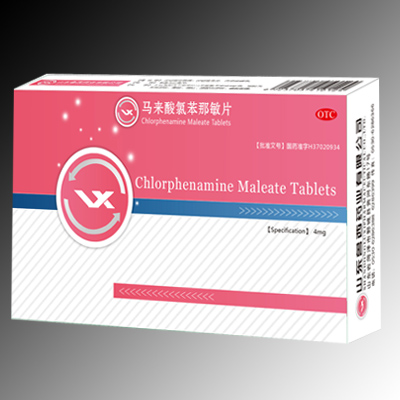

馬來酸氯苯那敏片

馬來酸氯苯那敏片 -